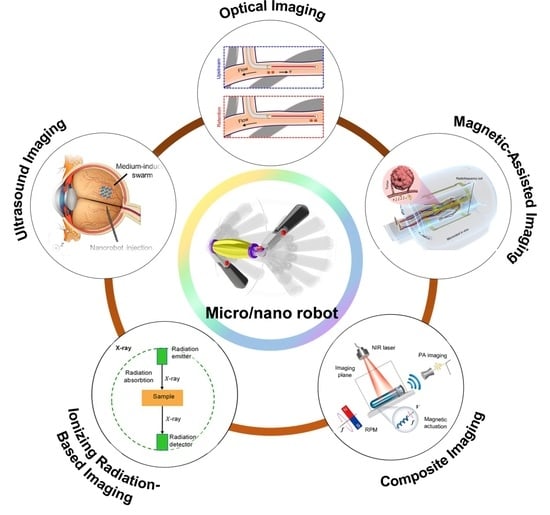

2. Micro/Nanorobot Imaging Techniques and Applications

2.1. Optical Imaging Technology

2.2. Magnetic Field-Assisted Imaging Techniques

2.3. Ultrasound Imaging (Ultrasound)

2.4. Ionizing Radiation-Based Techniques

2.5. Composite Imaging Techniques